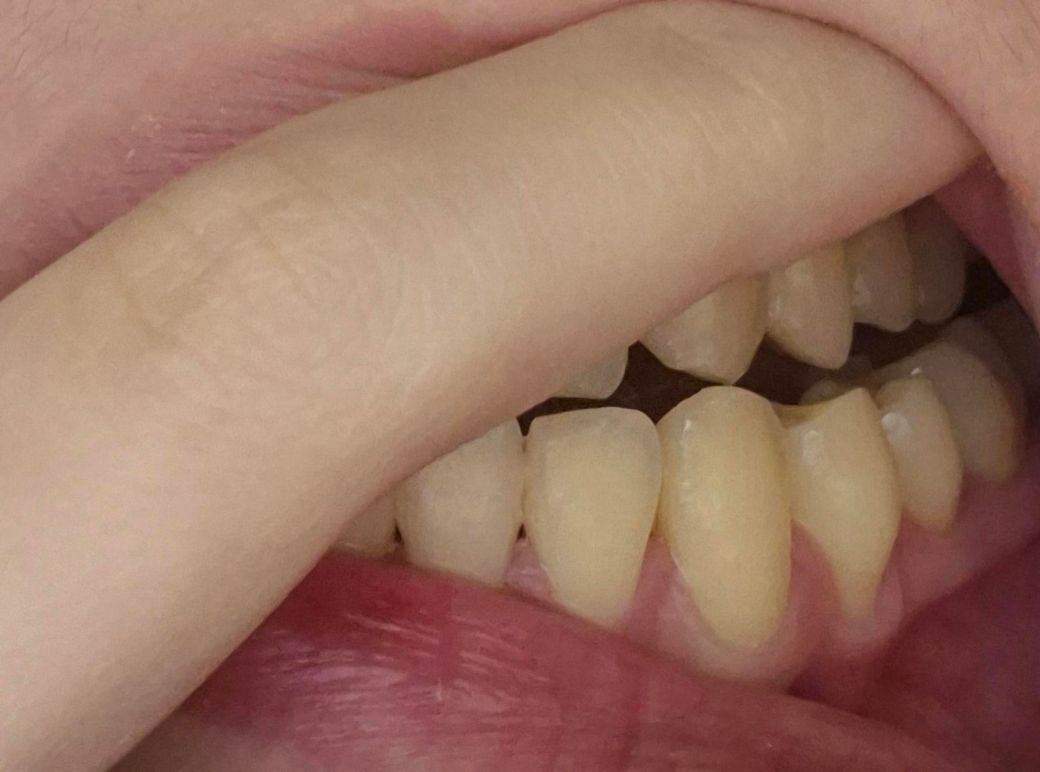

24살 여자 잇몸 퇴축이 심한 걸까요?

잇몸퇴축이 너무 심한 거 같은데 치료가 필요할까요?

• 1번 째 사진

사진으로 봤을 경우에는 잇몸 퇴축이 조금 진행된 것으로 보입니다. 잇몸 대축은 잇몸에 너무 강한 자극이 가해지면서 생기기 때문에 양치질을 할 때 잇몸에 넘어가는 자극이 가해지지 않다고 하는 것이 좋습니다.

나이 대비하여 잇몸이 조금 퇴축된 것은 맞습니다. 지금부터 관리를 더 잘해주셔야겠습니다.

송곳니는 원래 잇몸퇴축이 다른 치아보다 먼저, 더 많이 이뤄집니다 교정 후 잇몸퇴축이 동반되는 것은 흔한 부작용 중 하나이고요 앞으로 잇몸관리 꾸준히 치과에서 받으세요